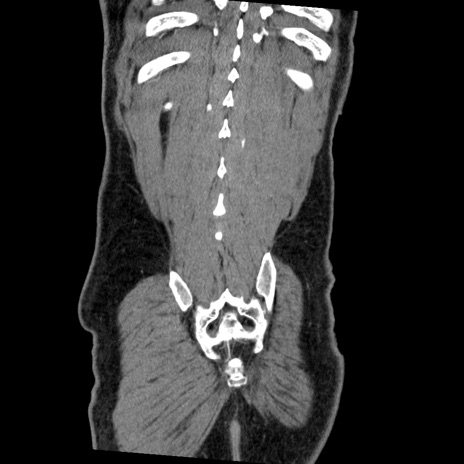

症例22(冠状断像)

【症例】50歳代男性

【主訴】腹痛

【現病歴】AVMからの被殻出血のため回復期リハ病棟入院中。 本日午後3時頃急に下腹部痛が出現した。

【既往歴】AVM、被殻出血、虫垂炎、高血圧

【身体所見】意識晴明、左半身不全麻痺、会話の理解は良好、36.5°C、腹部:膨隆、全体に板状硬、下腹部正中に圧痛点あり、反跳痛-、筋性防御不明、右下腹部にope scar

【データ】WBC 9400、CRP 0.06